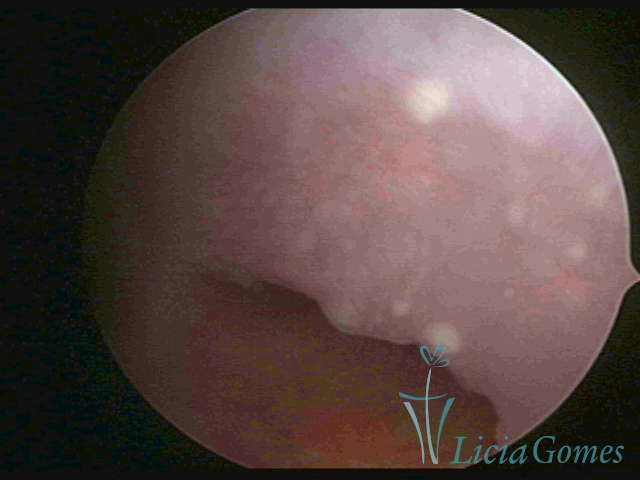

First part or proximal section or lower section:

During the proliferative phase, a light, crystalline mucus with a low adherence to the scope is found. The crypts and buds are a little swelled and vascularized, microvesicular, resembling grape clusters.